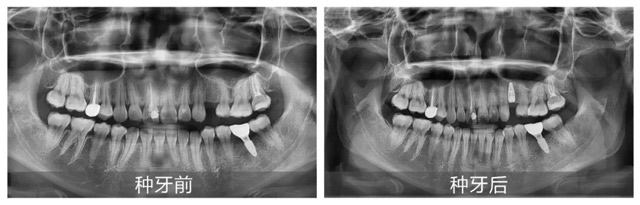

周女士术前术后拍片对比